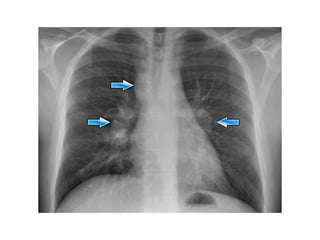

• Enlargement of the hili is usually due to

lymphadenopathy or enlarged vessels.

• In this case there is an enlarged hilar shadow on

both sides.

This could be the result of enlarged vessels or

enlarged lymph nodes.

A very helpful finding in this case is the mass on

the right of the trachea.

• This is known as the 1-2-3 sign in sarcoidosis, i.e.

enlargement of left hilum, right hilum and

paratracheal.

• Enlargement ofthe hili is usually due to lymphadenopathy or enlarged vessels. • In this case there is an enlarged hilar shadow on both sides. This could be the result of enlarged vessels or enlarged lymph nodes. A very helpful finding in this case is the mass on the right of the trachea. • This is known as the 1-2-3 sign in sarcoidosis, i.e. enlargement of left hilum, right hilum and paratracheal.